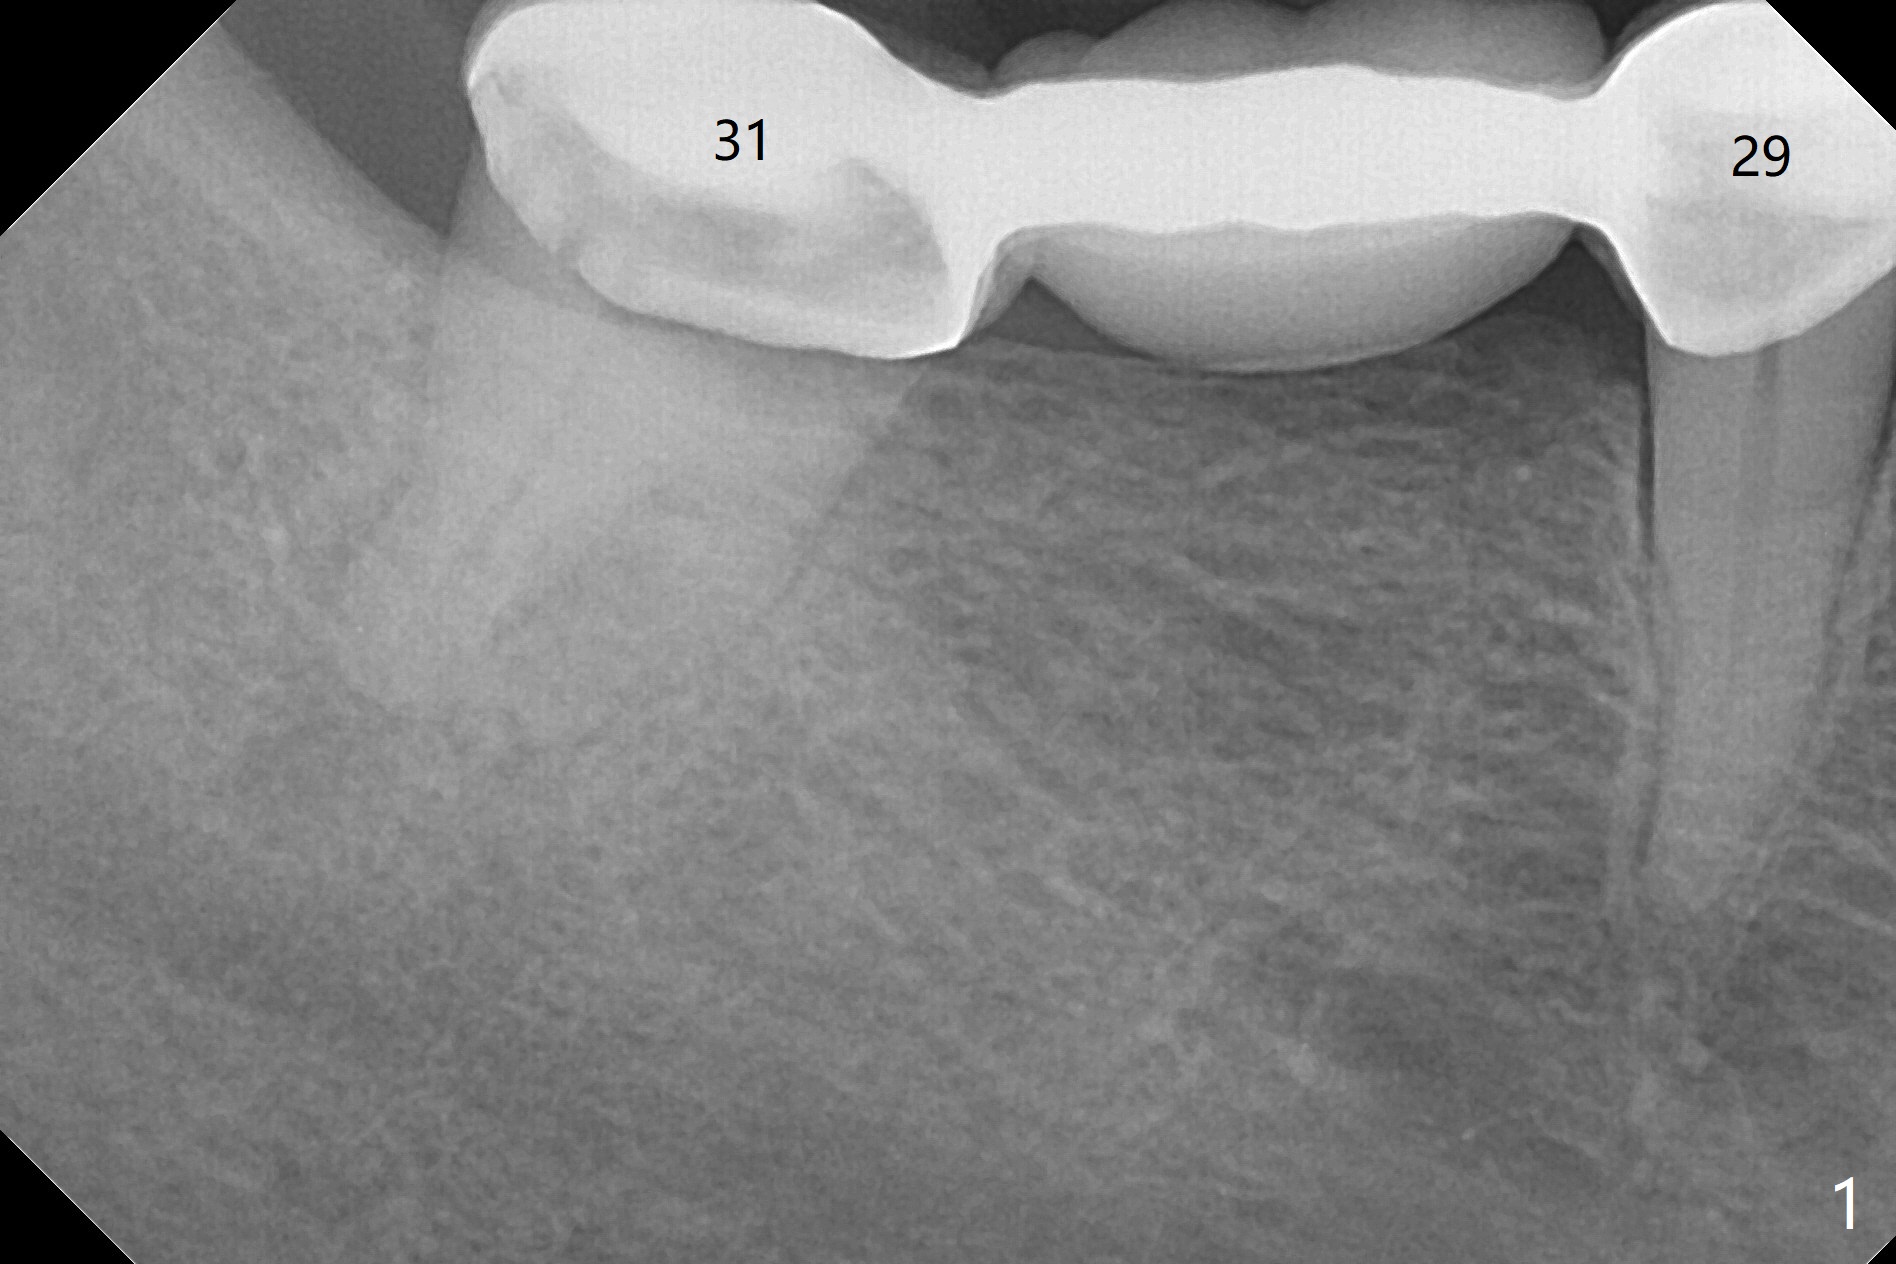

A 61-year-old woman with history of bruxism returns to clinic with chief complaint "I cannot chew bottom right. Top left has had pain and swelling before". Exam shows loose FPD at #31 (Fig.1) and necrosis of #14 (Fig.2). When the FPD is sectioned, the tooth #31 is found to have subgingival caries, filled with IRM (Fig.3). CT shows large PARL around MB and P roots of the tooth #14 (Fig.4), the fractured distal root of the tooth #19 with the low buccal plate (Fig.5) and a 5x10 mm implant being able to be placed at #30 (Fig.6). The crestal cortex (Fig.7 arrowheads) is thin in the edentulous area for several decades. The bone density is low (Fig.8, underprep). To place an implant over the pointed ridge, it should be trimmed prior to osteotomy (Fig.9). The bone loss associated with the fractured distal root is severe at #19 (Fig.10). After removal of the mesial root (Fig.11: 1), perform distal socket shield (2).